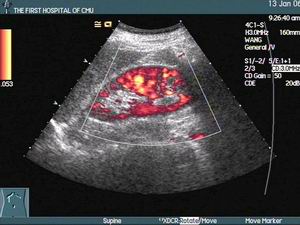

厭氧菌性肺炎影像圖實驗室檢查:

2.纖維支氣管鏡檢查 纖維支氣管鏡行雙套管取樣進行細菌培養,還可吸引膿液和病變部位注入抗生素,促進支氣管引流和膿腔的癒合。並有助於發現基礎病變。